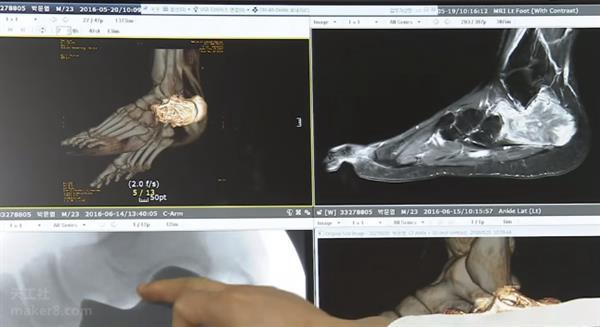

其次,政府支持在牙科治療設(shè)備和康復(fù)領(lǐng)域,創(chuàng)建可以提供個(gè)性化定制服務(wù)的3D打印設(shè)備。為了增強(qiáng)3D打印行業(yè)的競(jìng)爭(zhēng)力,韓國(guó)政府專(zhuān)注于新一代醫(yī)學(xué)、生物技術(shù)和智能材料,推動(dòng)這些需求強(qiáng)勁的行業(yè)發(fā)展。

在醫(yī)療行業(yè),韓國(guó)也探索了3D打印設(shè)備的快速審批。2016年5月23日,韓國(guó)食品藥品安全部( Ministry of Food and Drug Safety)官員稱(chēng),他們正在研究允許通過(guò)3D打印機(jī)制造的醫(yī)療儀器,在獲得政府最終批準(zhǔn)之前進(jìn)行有限度使用的可能性。這將使這些3D打印儀器能夠一次性地用于某些緊急情況下,甚至在政府最終批準(zhǔn)它們的醫(yī)學(xué)應(yīng)用之前。